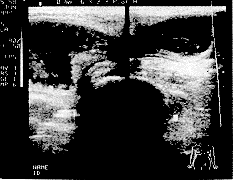

本组病例全部于腹股沟区探及混合性肿块回声,其中股疝于腹股沟韧带下方,大腿根部内前方探及肿块回声,肿块大小范围为19mm×33mm至35mm×49mm,多数能见囊壁回声,形态常呈梨形,上端尖、下端圆钝,部份呈半球形。内部以液性暗区为主,液暗区内可见实质光点、光团及肠管壁回声(图1)。腹腔内见多条肠管扩张,内径26~32mm,肠管腔内见液性暗区及增强光点来回流动。肿块常可探及疝颈及疝环、呈一管状暗区,内径为6~8mm。腹腔内容物由此与疝囊相通(图2)。

见腹腔内容构通过疝环进入疝囊

图1 左侧腹股沟疝嵌顿

腹腔肠管明显扩张,肠壁上粘膜皱壁清晰可见

图2 左侧腹股沟疝嵌顿并肠梗阻